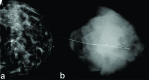

Screening mammography increases detection of non-palpable breast lesions requiring image-guided localization prior to surgery. Accurate preoperative localization is crucial for successful surgical outcomes. Wire-guided localization is currently the most widely used localization method for non-palpable breast lesions; however, this technique has multiple disadvantages including patient discomfort, possible wire transection and migration, suboptimal surgical incision placement due to wire location and limited scheduling flexibility decreasing operating room efficiency. As a result, promising new techniques including radioactive seed localization, non-radioactive radar localization and magnetic seed localization have been developed as alternatives. In this article, we provide an overview of these techniques and discuss their advantages, drawbacks and currently available outcome data.